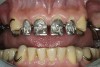

Initial examination revealed a partial edentulous patient with extensive wear of the maxillary anterior teeth and moderate wear in the mandibular teeth (Figure 1, Figure 2, Figure 3 , Figure 4, Figure 5, Figure 6 and Figure 7). The patient's maxillary and mandibular RPDs also showed excessive wear and multiple signs of fractures (Figure 2 and Figure 3). The patient had been wearing a mandibular nightguard for 8 years.

Figure 1  Intraoral anterior view of the patient presenting a severely worn maxillary dentition and loss of OVD.

Figure 1